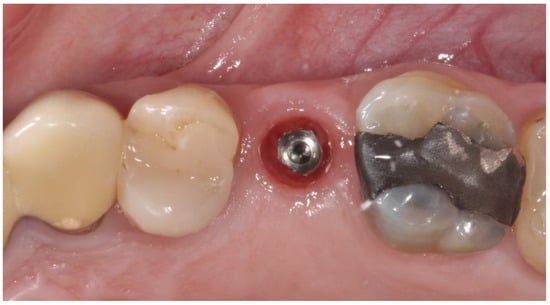

2.2. Surgical Procedures

2.3. Prosthetic Protocol